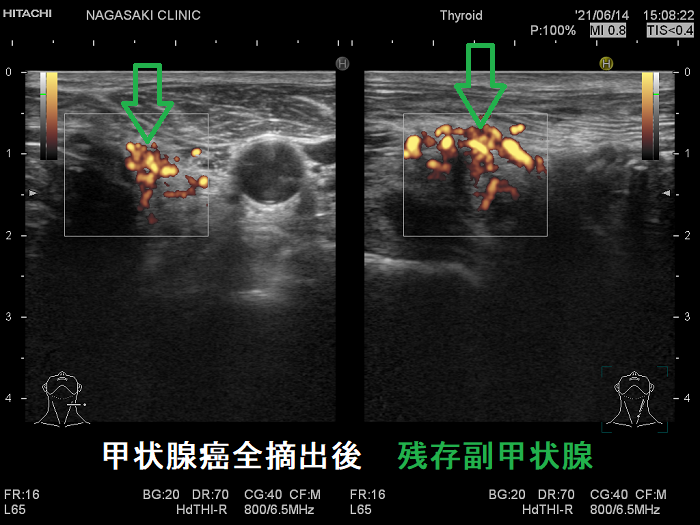

- 甲状腺摘術後、TSH 抑制療法;バセドウ病/甲状腺腫瘍で甲状腺切除と同時に副甲状腺も取ってしまった場合、取らずに温存した場合でも副甲状腺への血管を傷つけた場合

- 甲状腺全摘術時、副甲状腺も1-4腺を同時切除、あるいは切除しなくても栄養血管を損傷

- 術後副甲状腺機能低下症による低カルシウム血症;術直後のみならず、10年~30年以上して著明な低カルシウム血症で発症する事もある(日腎会誌 2012;54(1):40-47.)(J Clin Diagn Res. 2017 Feb; 11(2): OD07–OD09.)。

ケース①

ケース②